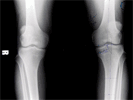

62 years old lady with severe varus both knees and osteoarthritis

Pre

Op

Pre Operation Xrays of limb